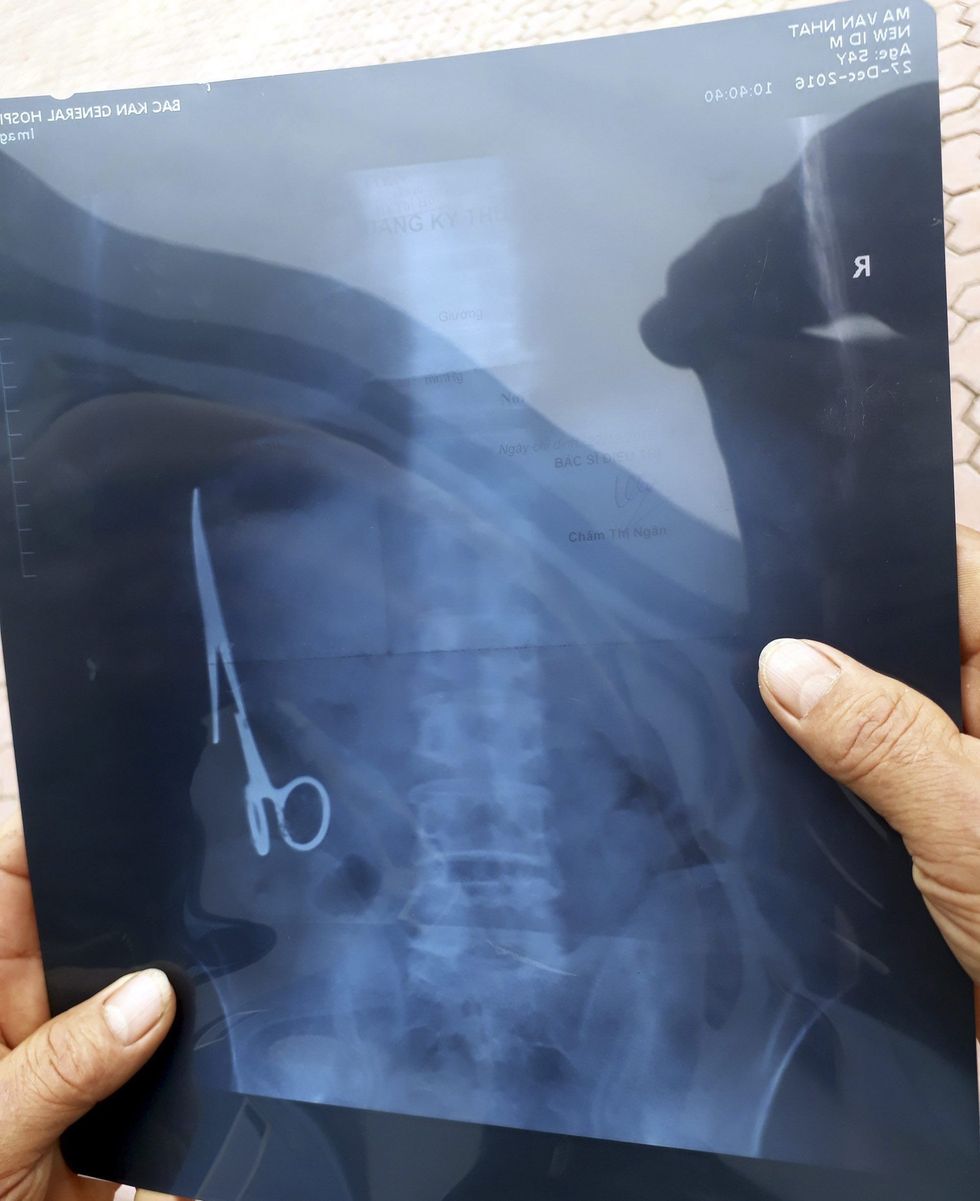

Pas 18 vitesh ia nxorën nga barku gërshërët e harruara gjatë operimit (Foto)

Ma Van Nhat nga Vietnami, për 18-vjet i ka mbajtur në bark një palë gërshërë, që ia kishin harruar gjatë operimit.

Mirëpo, mjekët nuk kanë qenë të kujdesshëm dhe ia kanë lënë brenda gërshërët, para se t’ia qepnin lëkurën.

Meqenëse kishte dhimbje, 54-vjeçari ka shkuar në spital për kontroll ku ka kuptuar se çfarë ka brenda trupit.

Për t’i nxjerrë objektin metalik, është realizuar operacioni prej tre orësh, i kryer nga një ekip ekspertësh të kirurgjisë.